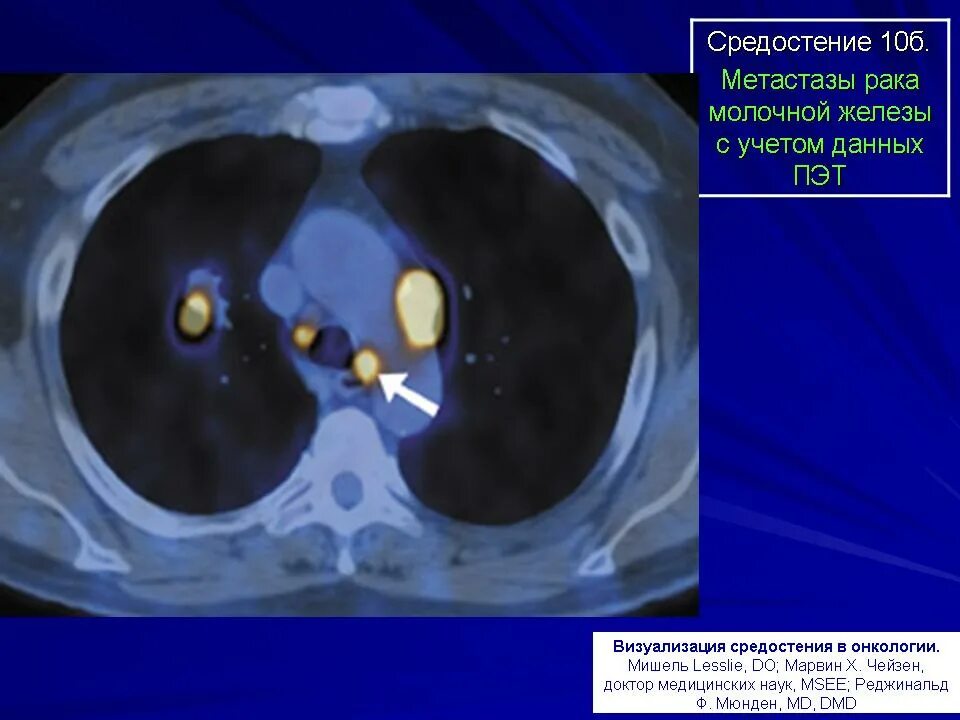

Метастазы в средостении легких